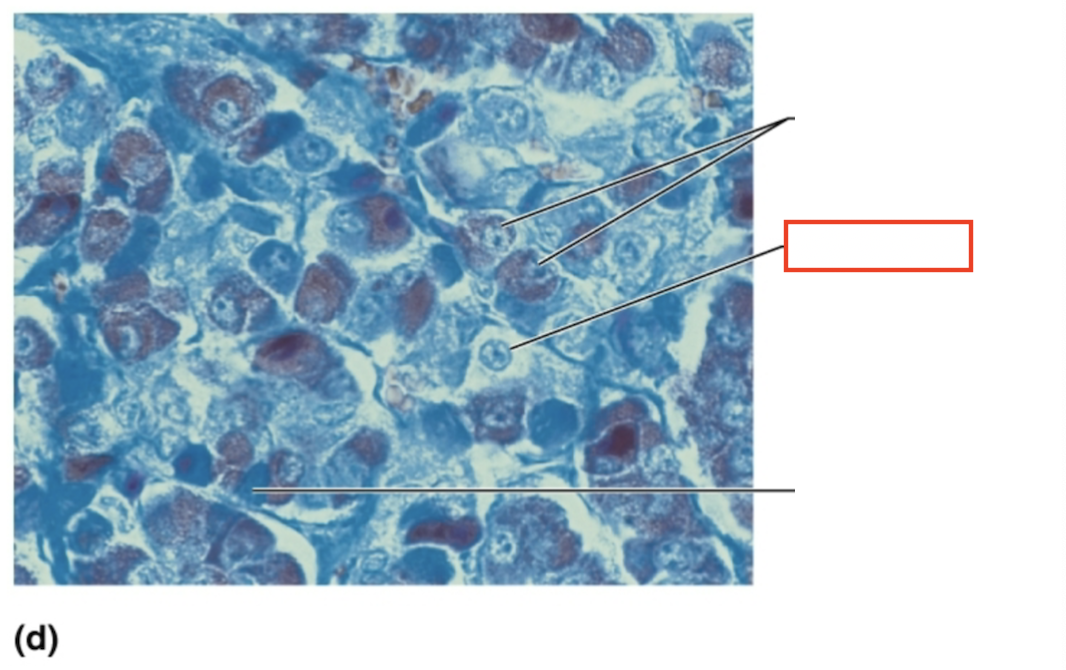

What structure is highlighted?

acidophils

What structure is highlighted?

chromophobe

What structure is highlighted?

basophil

What tissue is shown?

anterior pituitary